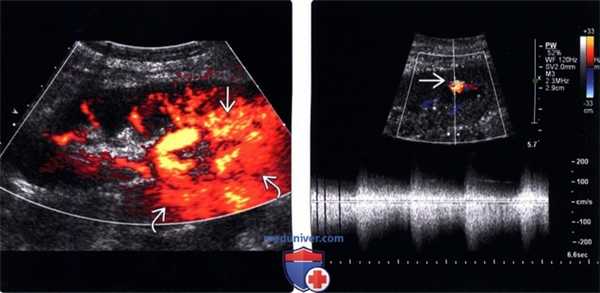

3. Артериовенозная фистула трансплантата:

• В типичных случаях - участок в почке с артефактом наложения и вибрированием тканей.

• Высокоскоростная спектрограмма с низкой резистентностью

• После биопсии